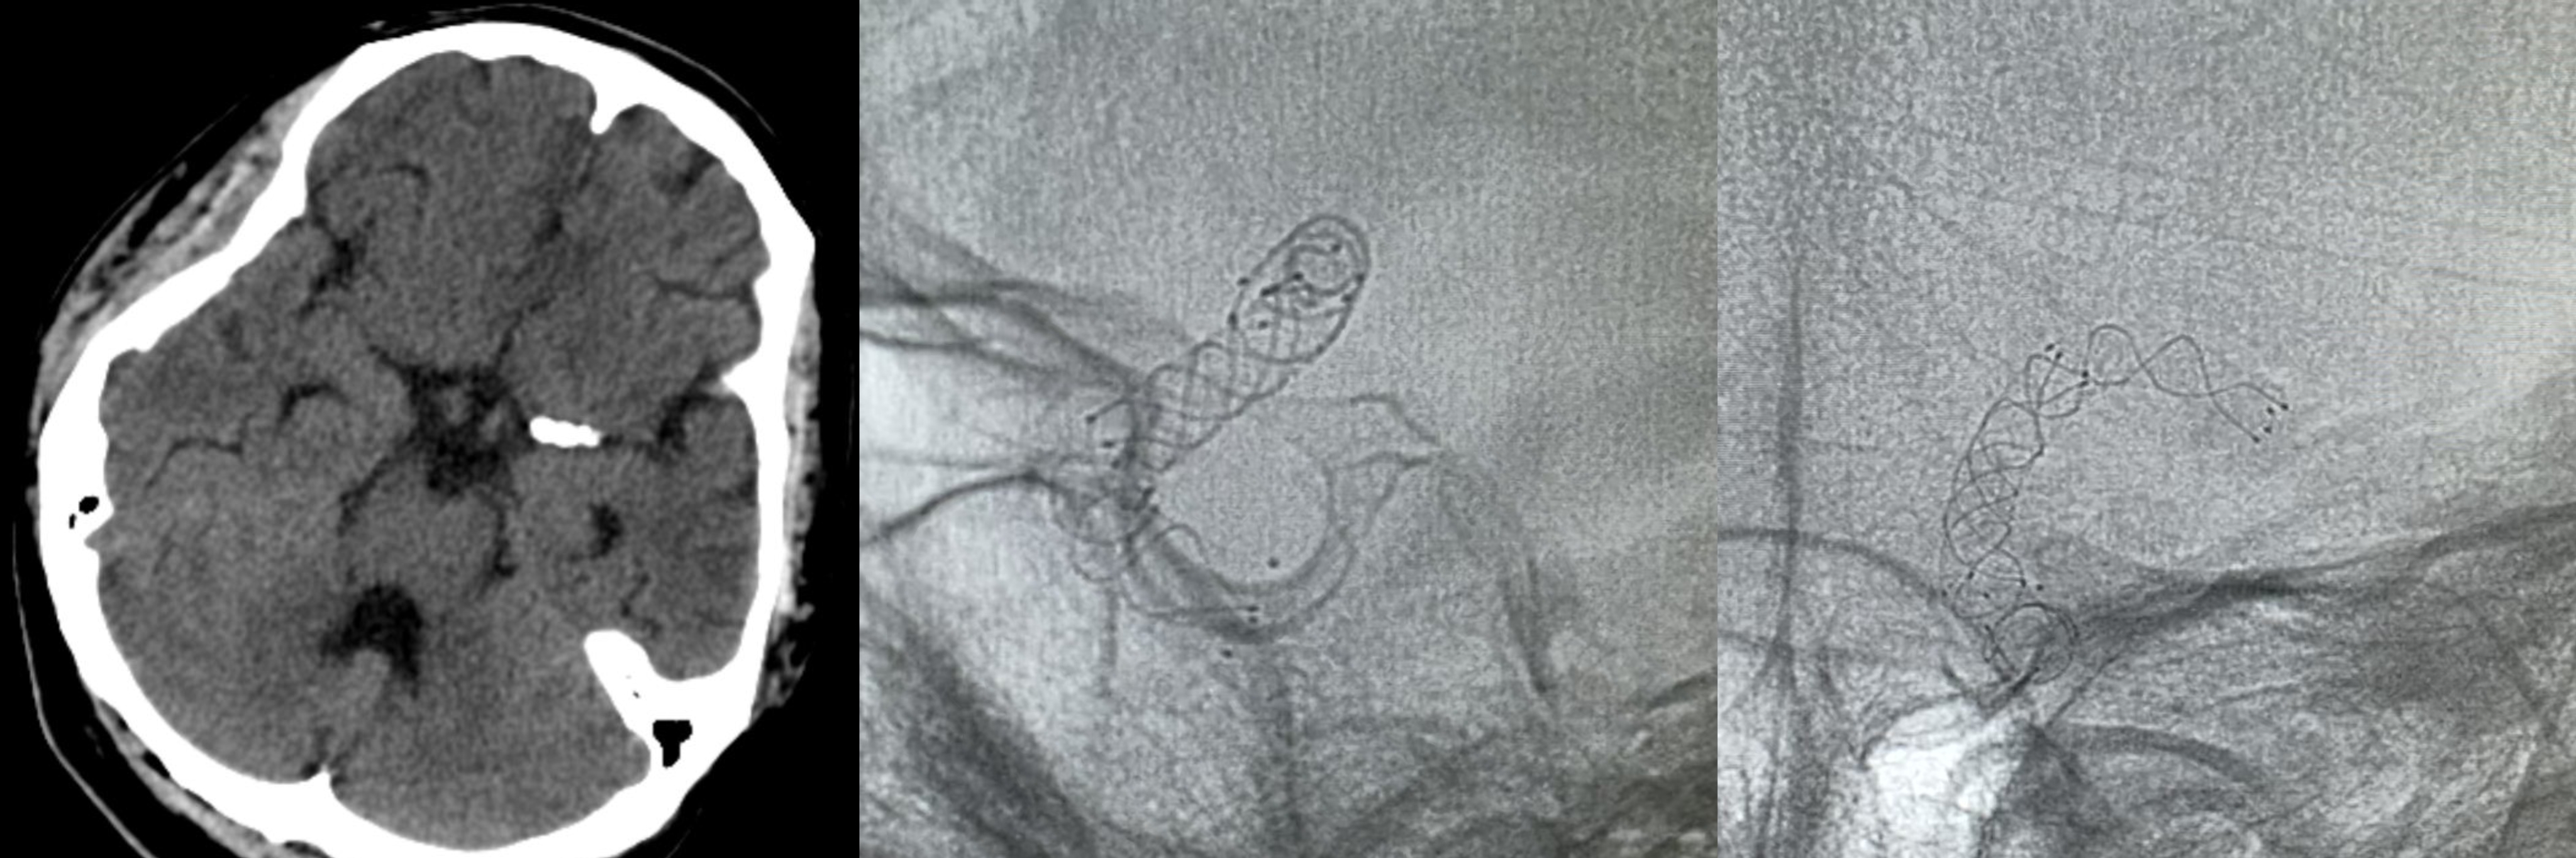

▲DSA显示左侧颈内动脉眼动脉段血泡样动脉瘤,直径约1mm

神经外科脑血管病介入团队采取微创治疗,于载瘤动脉内套叠释放两枚编织支架,起到血流导向作用,部分阻断了进入动脉瘤的血流,降低了再出血风险。术后入住ICU,予机械通气,镇静镇痛、防治脑血管痉挛、脱水等治疗。定期复查头颅CT未再出血,无脑梗死及脑积水。患者病情逐渐好转,1个月后转至当地康复医院继续治疗。出院时患者神志清楚,可进食,混合性失语,左侧肢体不完全偏瘫。

▲术后影像可见套叠支架,动脉瘤处网孔密度较高